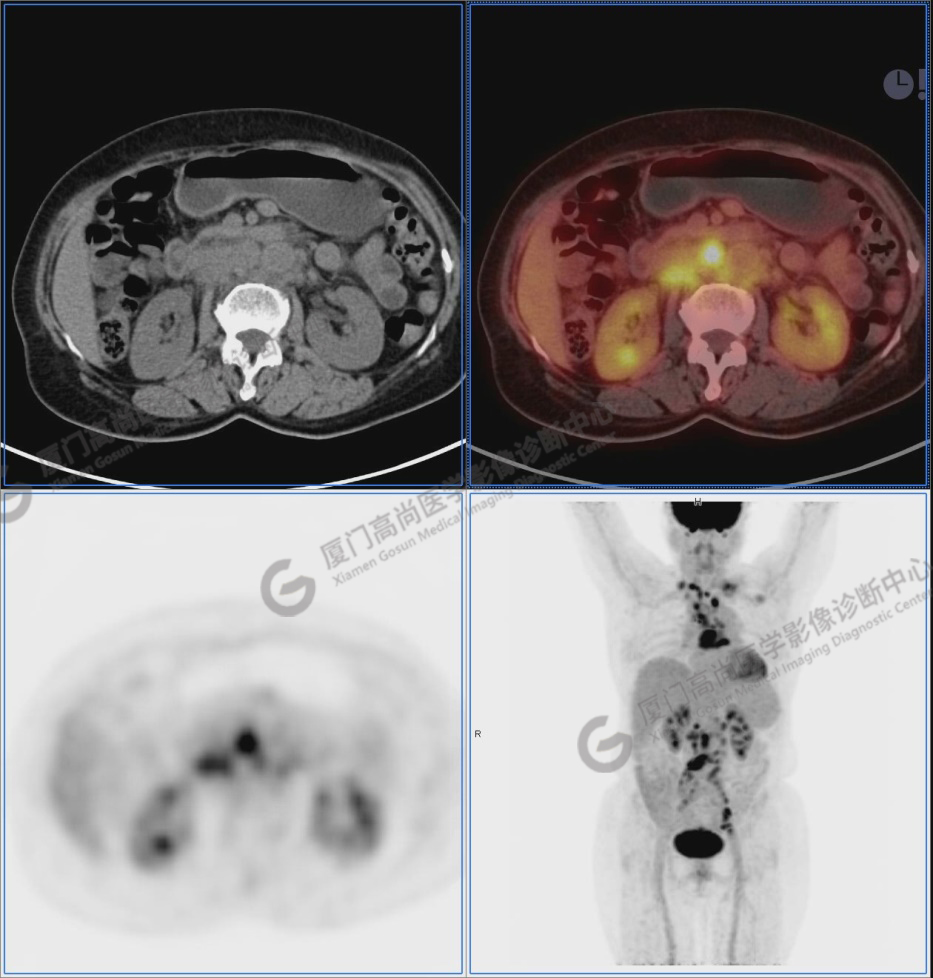

圖1:PET/CT全身圖像

圖2-9:雙側(cè)鎖骨區(qū)、縱隔、右側(cè)內(nèi)乳區(qū)、腸系膜緣、腹膜后、雙側(cè)髂血管旁及盆腔多發(fā)腫大淋巴結(jié)影,代謝不同程度增高,考慮為轉(zhuǎn)移。